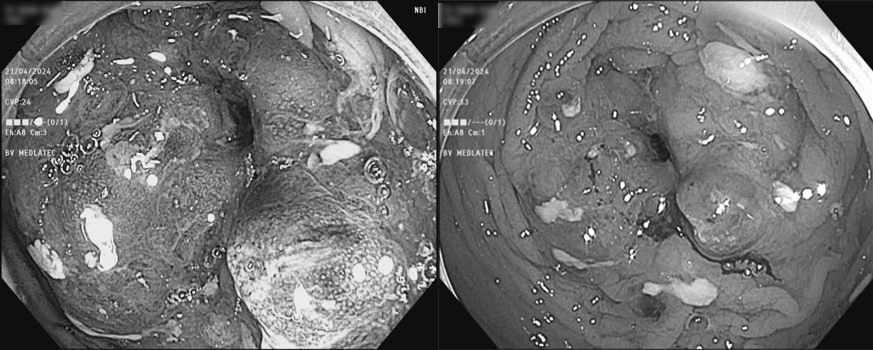

Hình ảnh nội soi phát hiện nhiều tổn thương sùi loét chiếm hết lòng trực tràng. Ngay lập tức, bác sĩ tiến hành sinh thiết tại bờ khối sùi và chuyển mẫu về Trung tâm Giải phẫu bệnh MEDLATEC phân tích, cho kết quả Carcinoma tuyến biệt hóa vừa. Từ kết quả chẩn đoán của hai tiêu chuẩn “vàng” là nội soi và giải phẫu bệnh, bệnh nhân được xác định mắc ung thư đại trực tràng T3N2M0 (giai đoạn 3).

Hình ảnh nội soi phát hiện tổn thương sùi loét chiếm hết lòng trực tràng |